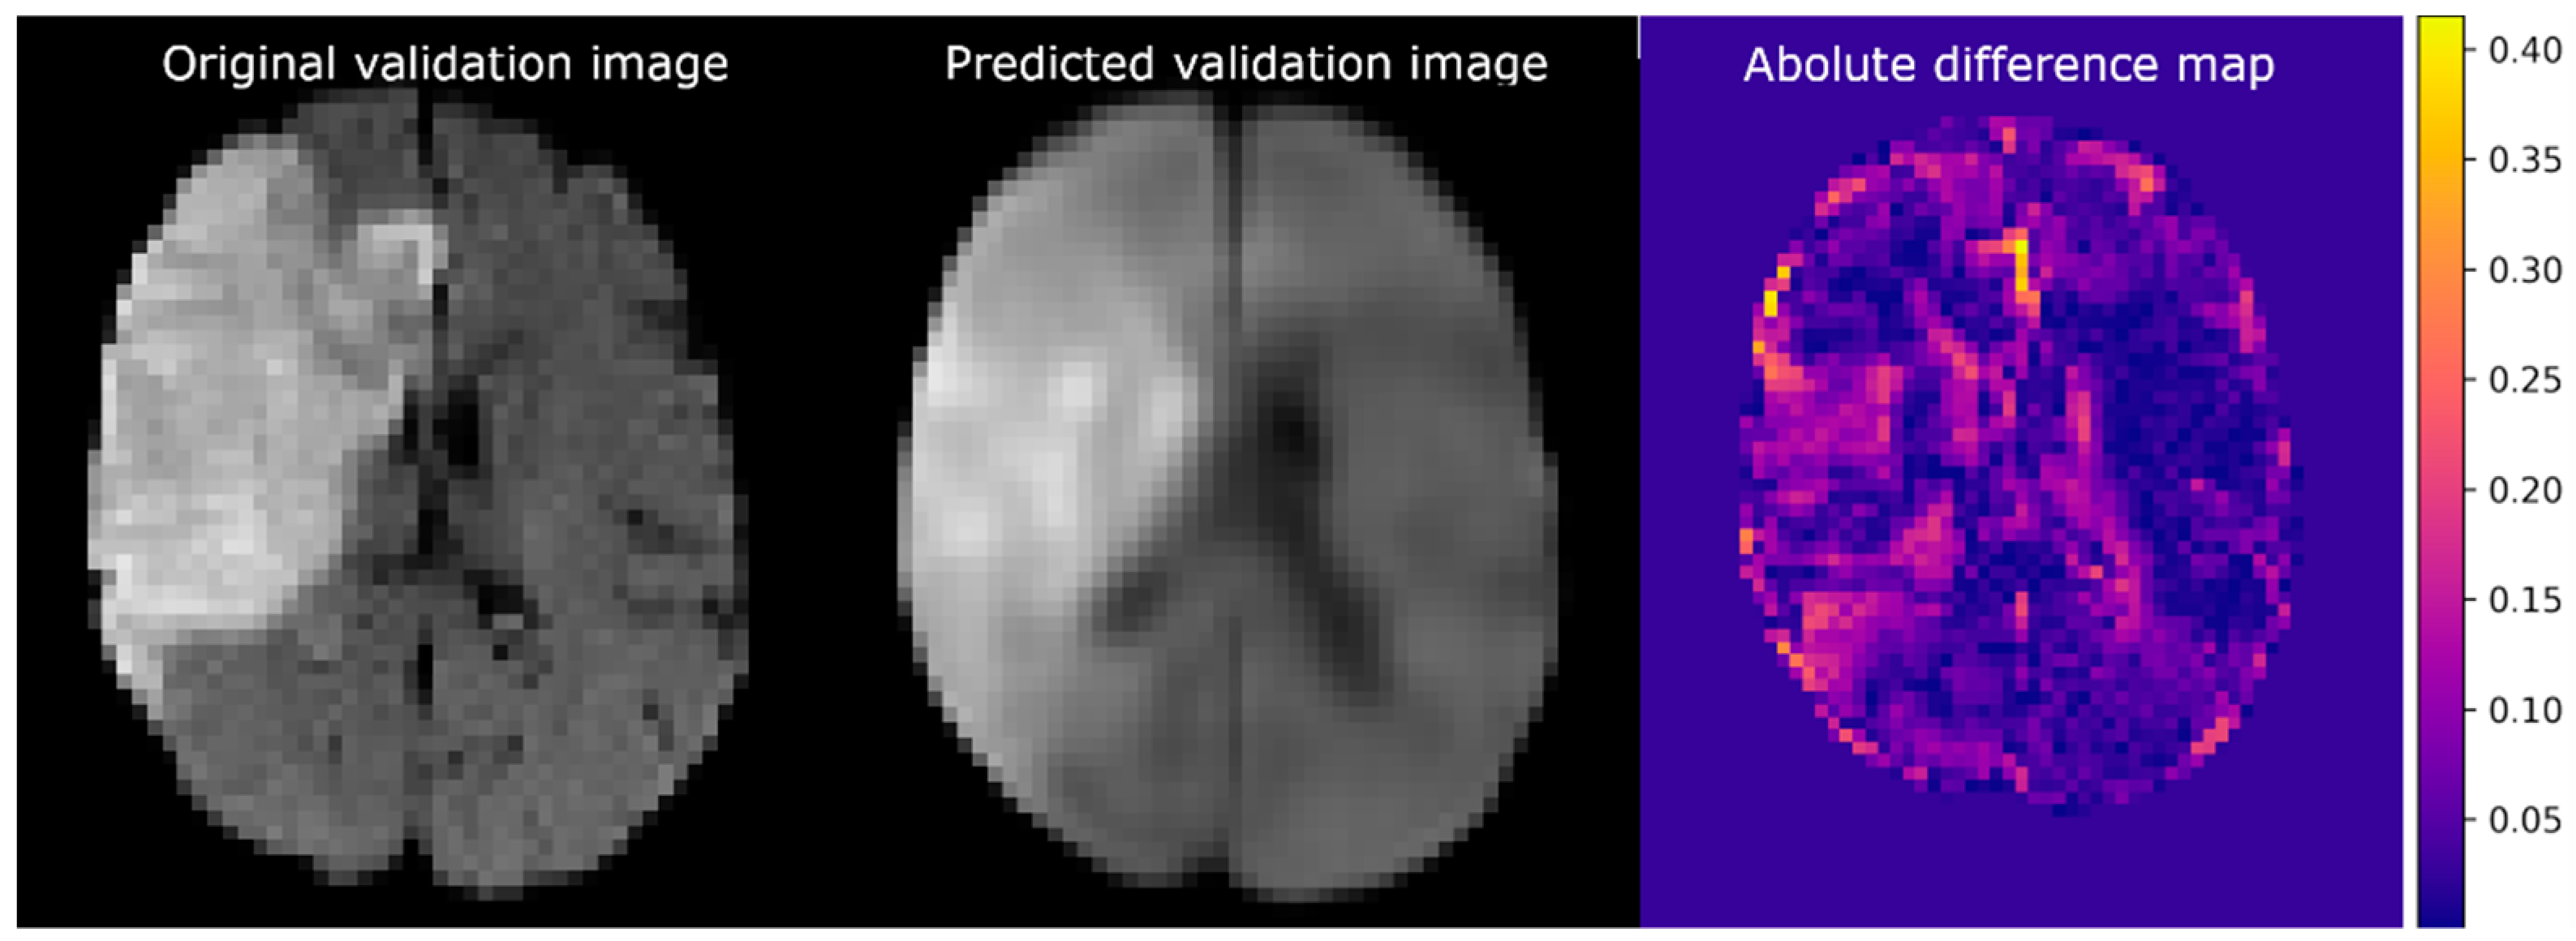

The training MSE of the CAE was 2.0 × 10−3 (arbitrary units), and the validation error was 5.1 × 10−3. Figure 4 shows the reconstruction of a validation image (left) established by the CAE (middle) and the corresponding difference map (right). The difference map shows small intensity differences in most of the healthy brain regions. The largest differences in intensities were present at the transition between brain tissue and cerebral spinal fluid. It is of note that some predicted voxels within the lesion and ventricles also differed in intensity from the original. The CAE was able to reconstruct the lesion at a location similar to that of the original image.

Figure 4.

Example of imaging reconstruction using a trained convolutional autoencoder. (Left) An axial slice of the original validation image. (Middle) The corresponding slice of the predicted image. (Right) The absolute difference between the normalized original and predicted images.